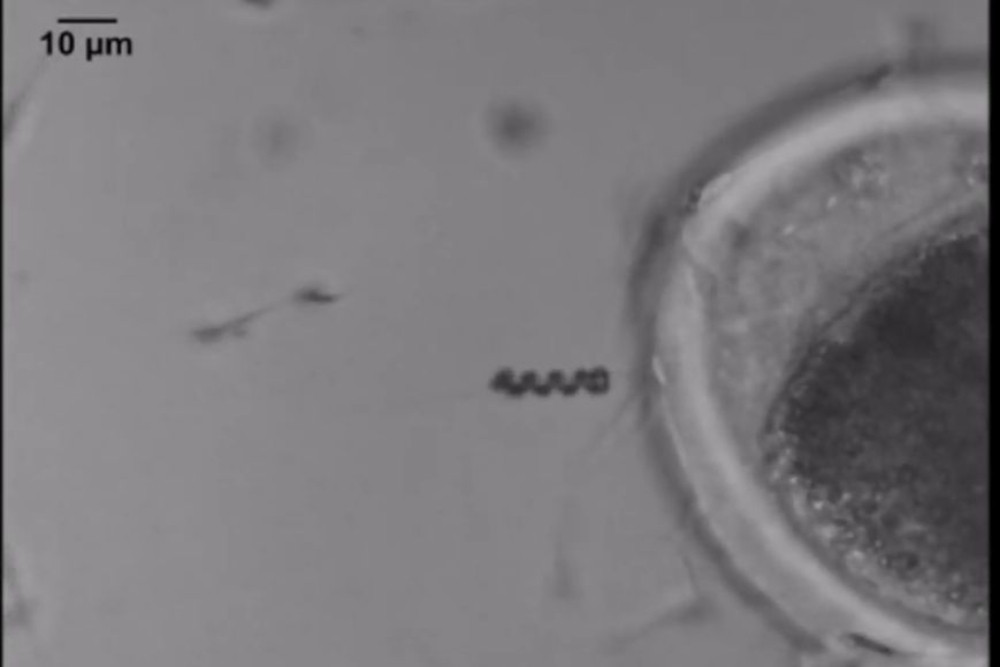

Saat ini, para peneliti telah mengembangkan spermbot sebagai inovasi dalam bidang nano robotik. Spermbot merupakan robot berukuran mikro atau nano yang bekerja bersama sel sperma atau meniru bentuk dan cara geraknya. Tujuannya adalah membantu sperma bergerak lebih terarah, kuat, dan efisien di dalam tubuh manusia.

Dalam jurnal International Journal of Nanomedicine, artikel berjudul “Spermbots and Their Applications in Assisted Reproduction: Current Progress and Future Perspectives” menjelaskan bahwa model spermbot dibagi menjadi tiga jenis utama:

Biohybrid spermbot

Model pertama ini menggunakan sperma asli yang dipasangi struktur nano berbentuk tabung, spiral, atau rangka kecil. Struktur ini biasanya bersifat magnetik dan membantu sperma bergerak lebih terarah menuju sel telur. Model ini cocok digunakan untuk kasus sperma yang lemah atau sulit bergerak.Robot mirip sperma

Berbeda dengan model pertama, jenis ini tidak menggunakan sel hidup. Robot dibuat menyerupai bentuk sperma atau ekor spiral dari bahan logam nano atau polimer. Model ini lebih banyak digunakan untuk keperluan penelitian, pengantar obat, serta eksperimen dalam sistem reproduksi.Cargo-carrying spermbot